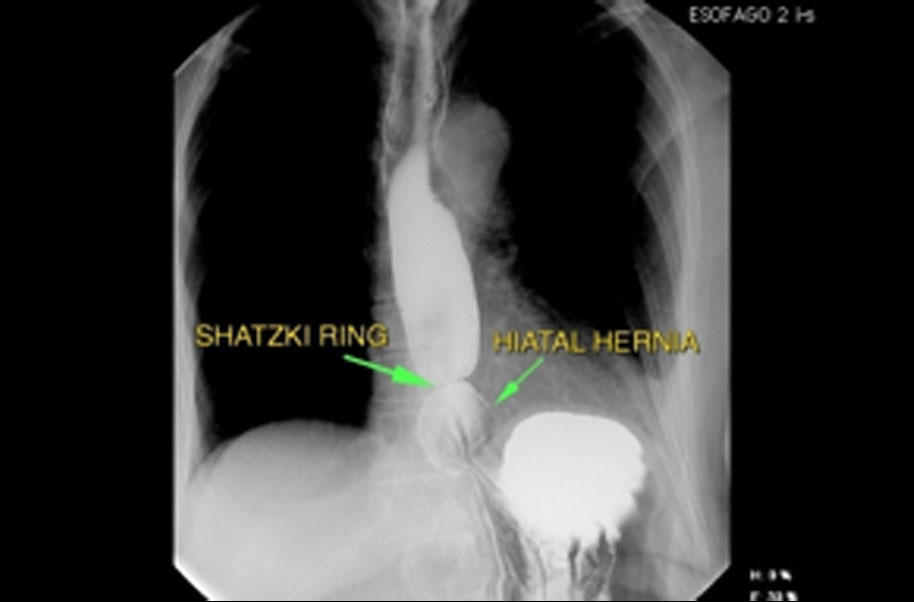

A schatzki ring or schatzki–gary ring is a narrowing of the lower esophagus that can cause difficulty swallowing (dysphagia). The narrowing is caused by a ring of mucosal tissue (which lines the esophagus) or muscular tissue.

Gastroesophageal reflux disease, also known as gerd, is a possible cause of schatzki ring formation. People with a schatzki ring often have acid reflux disease as well. Additionally, conditions that can lead to reflux disease, such as a hiatal hernia, are often found in people with a schatzki ring.